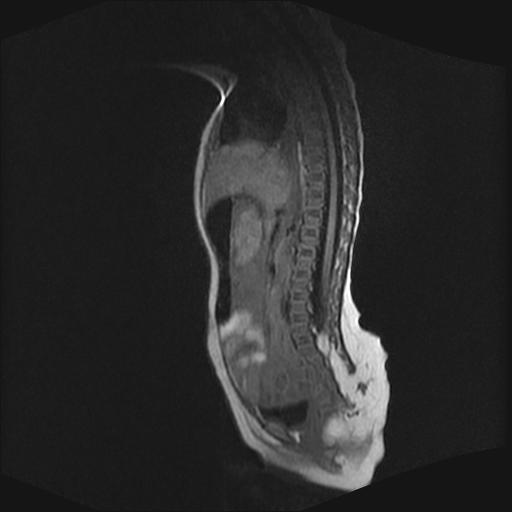

四个月的女婴,ct示脊膜膨出.

脂肪脊髓脊膜膨出

脊柱裂、脊膜膨出